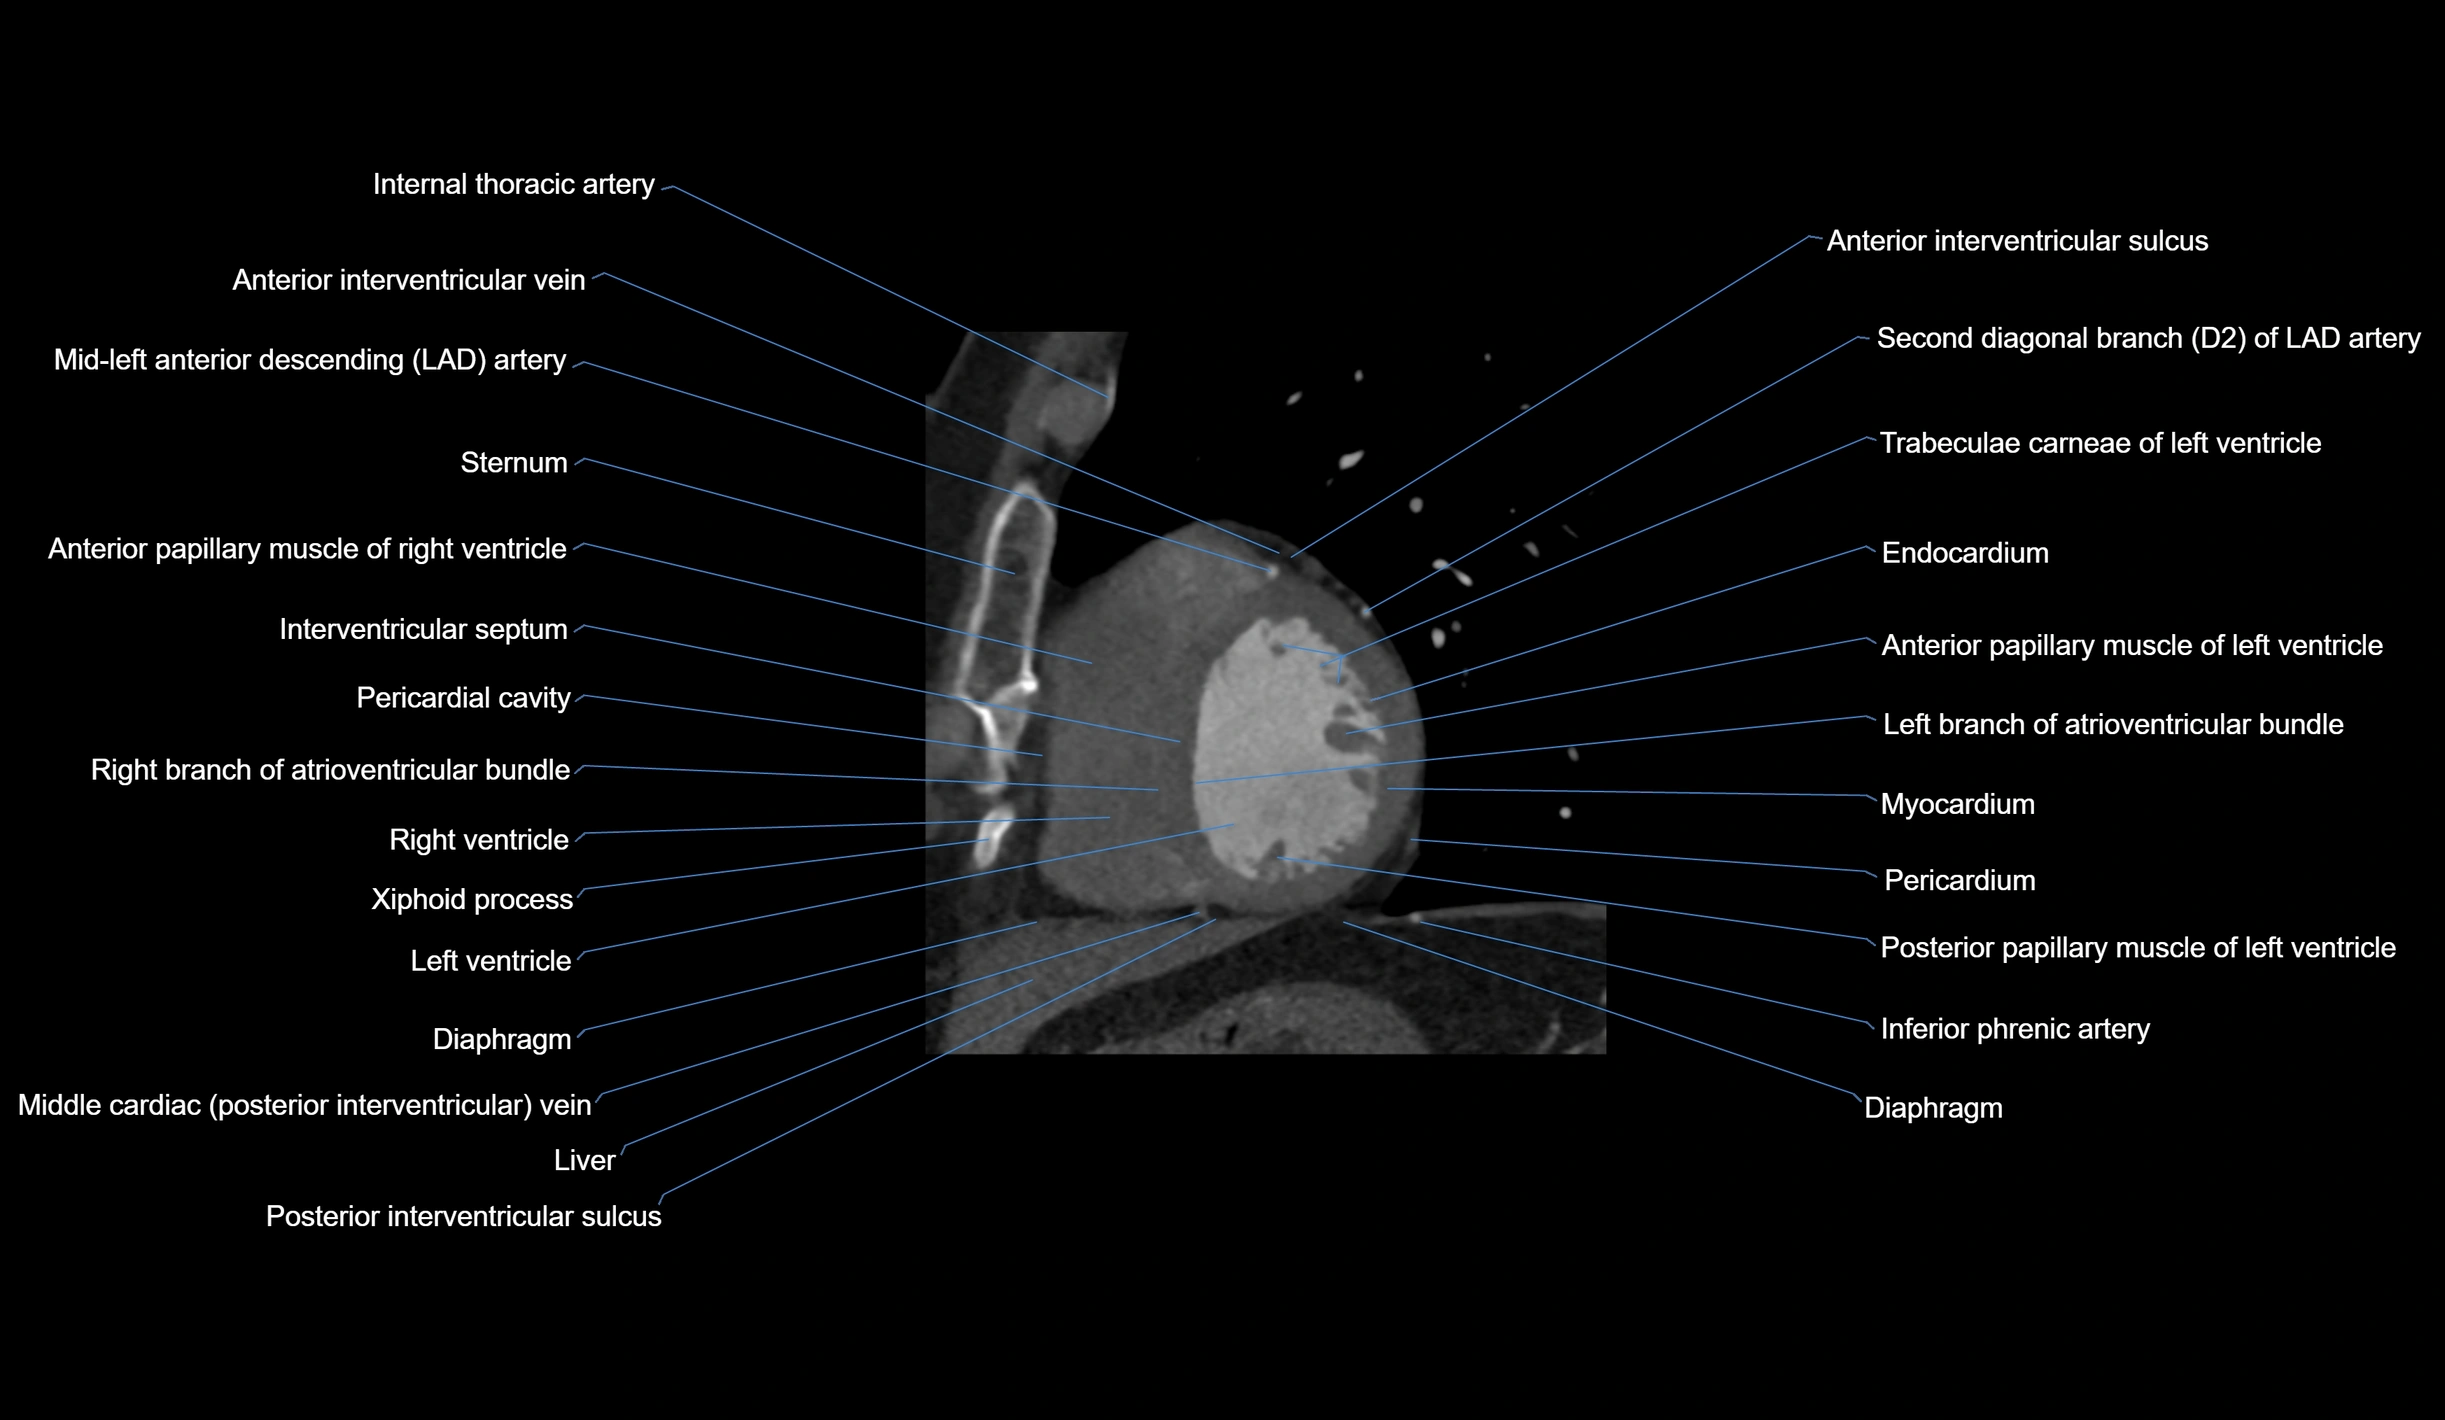

CT Appearance

Non-contrast CT (Calcium Scoring):

-

AM artery visualized for coronary calcium scoring

Calcified plaques appear as hyperdense foci; scored with Agatston method

CT Coronary Angiography (CCTA):

Best non-invasive modality for acute marginal artery visualization

Shows origin, course along the acute margin, and right ventricular branches

Detects stenosis, occlusion, calcified and non-calcified plaques, aneurysm, or anomalous course

Multiplanar reformats and 3D reconstructions help in pre-PCI and surgical planning

Critical for assessing right ventricular infarction risk in RCA disease

MRI image

CT images